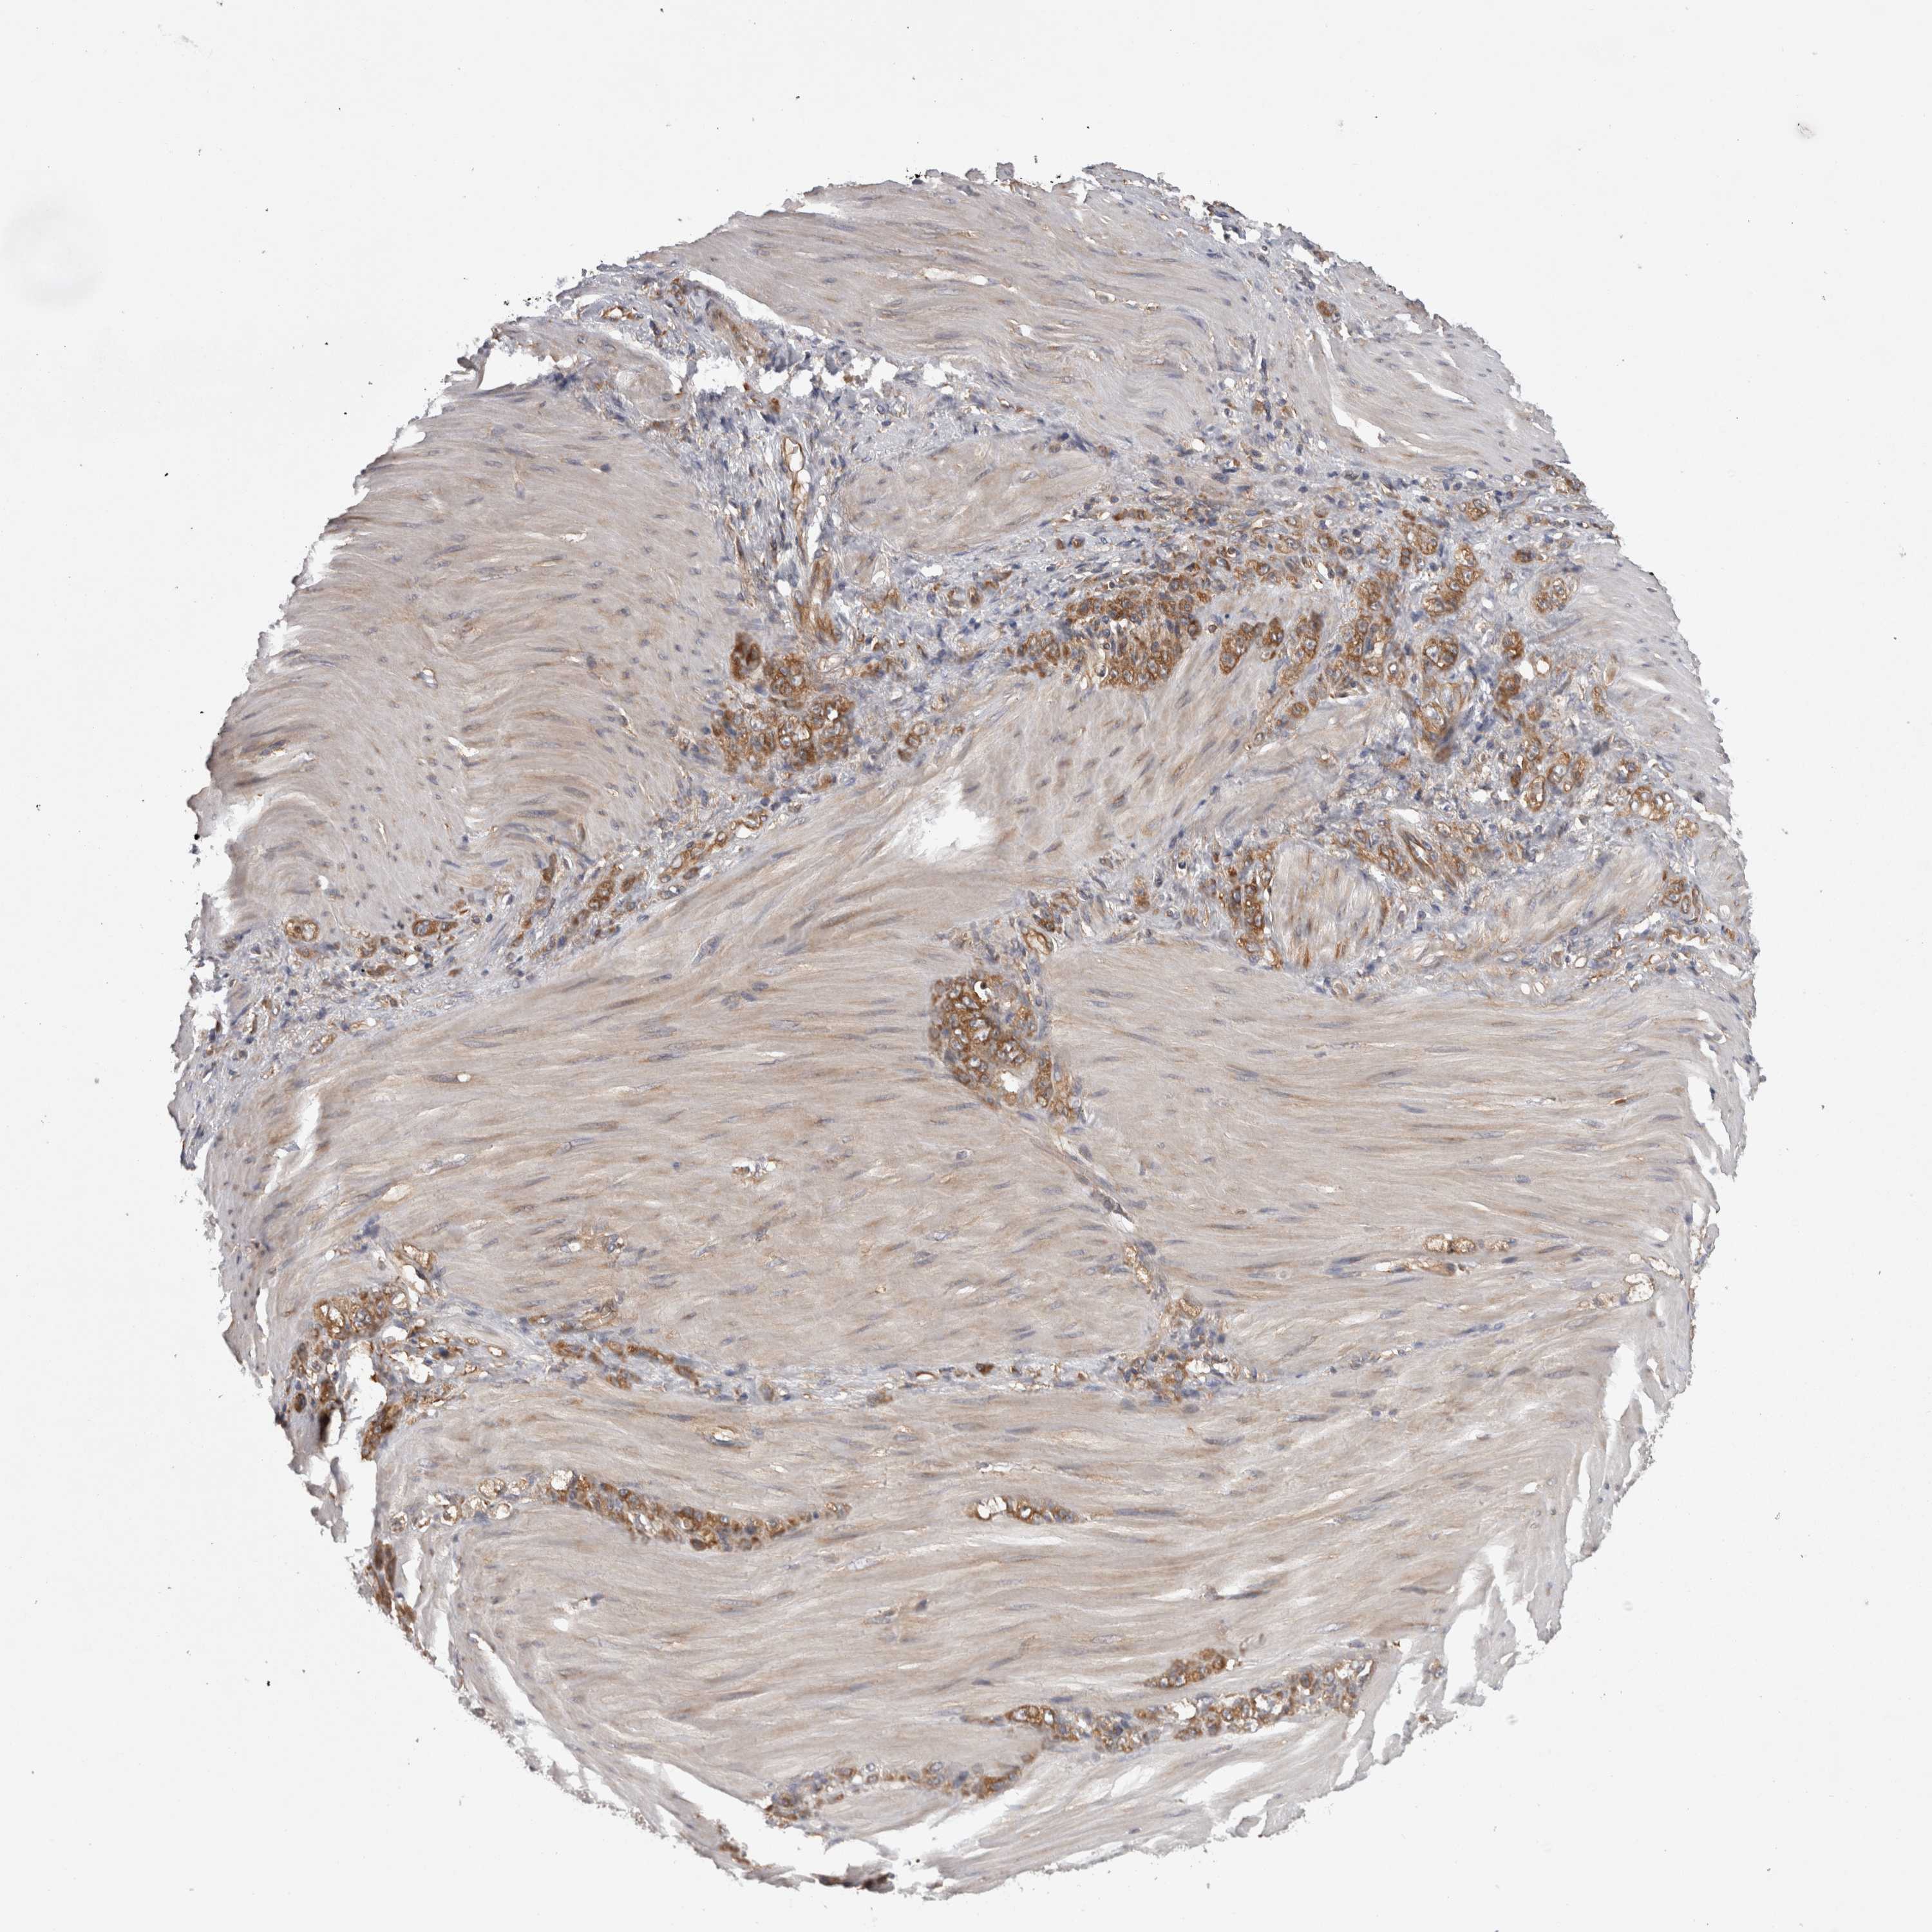

STOMACH CANCER - Protein expressioni

A mouse-over function shows sample information and annotation data. Click on an image to view it in a full screen mode. Samples can be filtered based on level of antibody staining by selecting one or several of the following categories: high, medium, low and not detected. The assay and annotation is described here.

Note that samples used for immunohistochemistry by the Human Protein Atlas do not correspond to samples in the TCGA dataset.

Antibody stainingi

Antibody staining in the annotated cell types in the current human tissue is reported as not detected, low, medium, or high, based on conventional immunohistochemistry profiling in selected tissues. This score is based on the combination of the staining intensity and fraction of stained cells.

Each image is clickable and will lead to virtual microscopy that enables deeper exploration of all samples and also displays staining intensity scores, fraction scores and subcellular localization as well as patient and tissue information for each sample.

Antibody HPA021557

Antibody HPA024646

Staining

High

Medium

Low

Not detected

Intensity

Strong

Moderate

Weak

Negative

Quantity

>75%

75%-25%

<25%

None

Location

Nuclear

Cytoplasmic/membranous

Cytoplasmic/membranous,nuclear

Adenocarcinoma, NOS